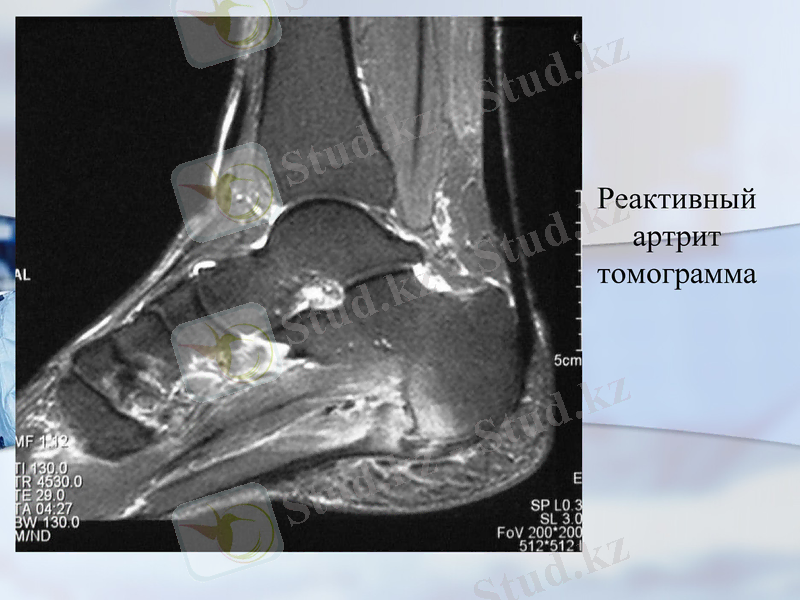

Реактивный артрит томограмма

4. МРТ